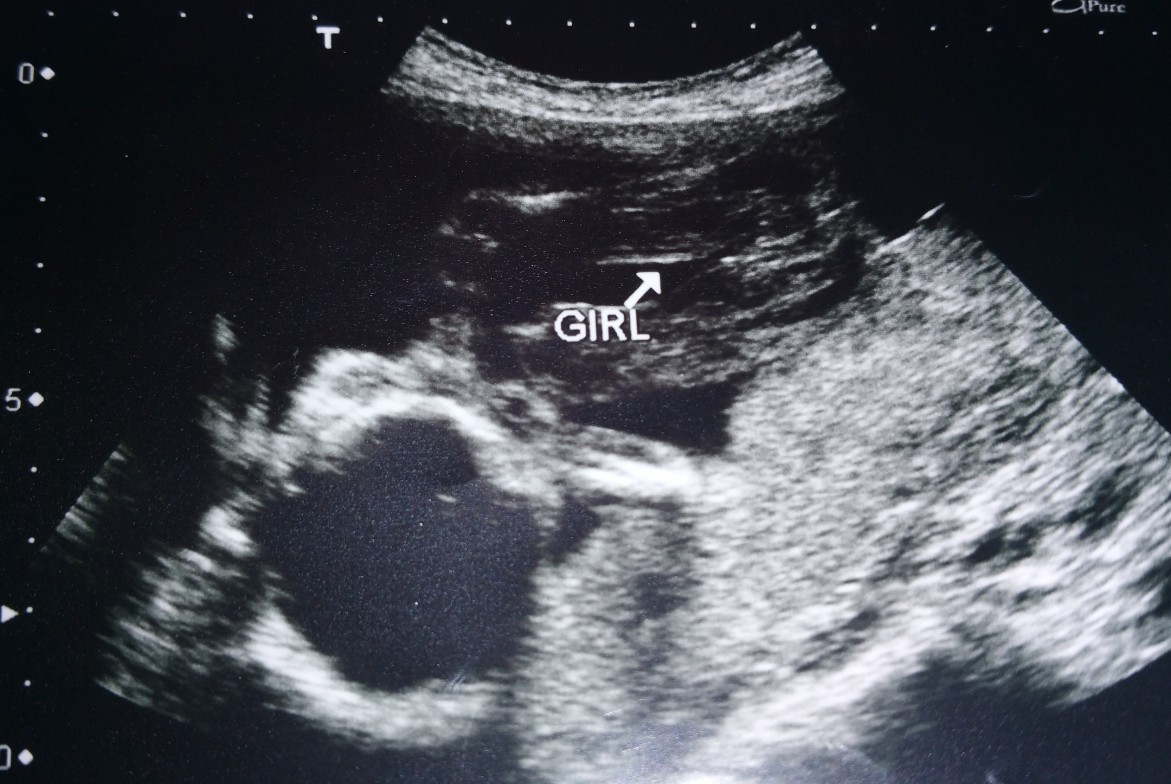

Hello ladies, I am new here but hoping I could have some opinions. I got a gender ultrasound at 20 weeks and doc is leaning towards girl, but the lines are rounded except for the one down the middle. Baby would not open their legs so it was tough I go for another soon, but I'm just wondering what you all think. Thanks!! :)

• I don't really know anything, but... I thought it was 2 lines for a boy and 3 lines for a girl. So my guess would be girl! x

• Ya its a tough call. My first doctor told me boy at 15 weeks when baby was spread eagle and then this doctor told me girl.

• I'm not sure how to read the sonograms. I've just gotten lucky when figuring out that my son was a boy when I saw the images and then the tech or doctor confirmed it for me and explained it. My best suggestion would be to wait until your next sonogram and tell your doc or tech your questions and/or confusions. I'm sure they'd explain it better than me, but I agree with the guess that it looks like a girl.